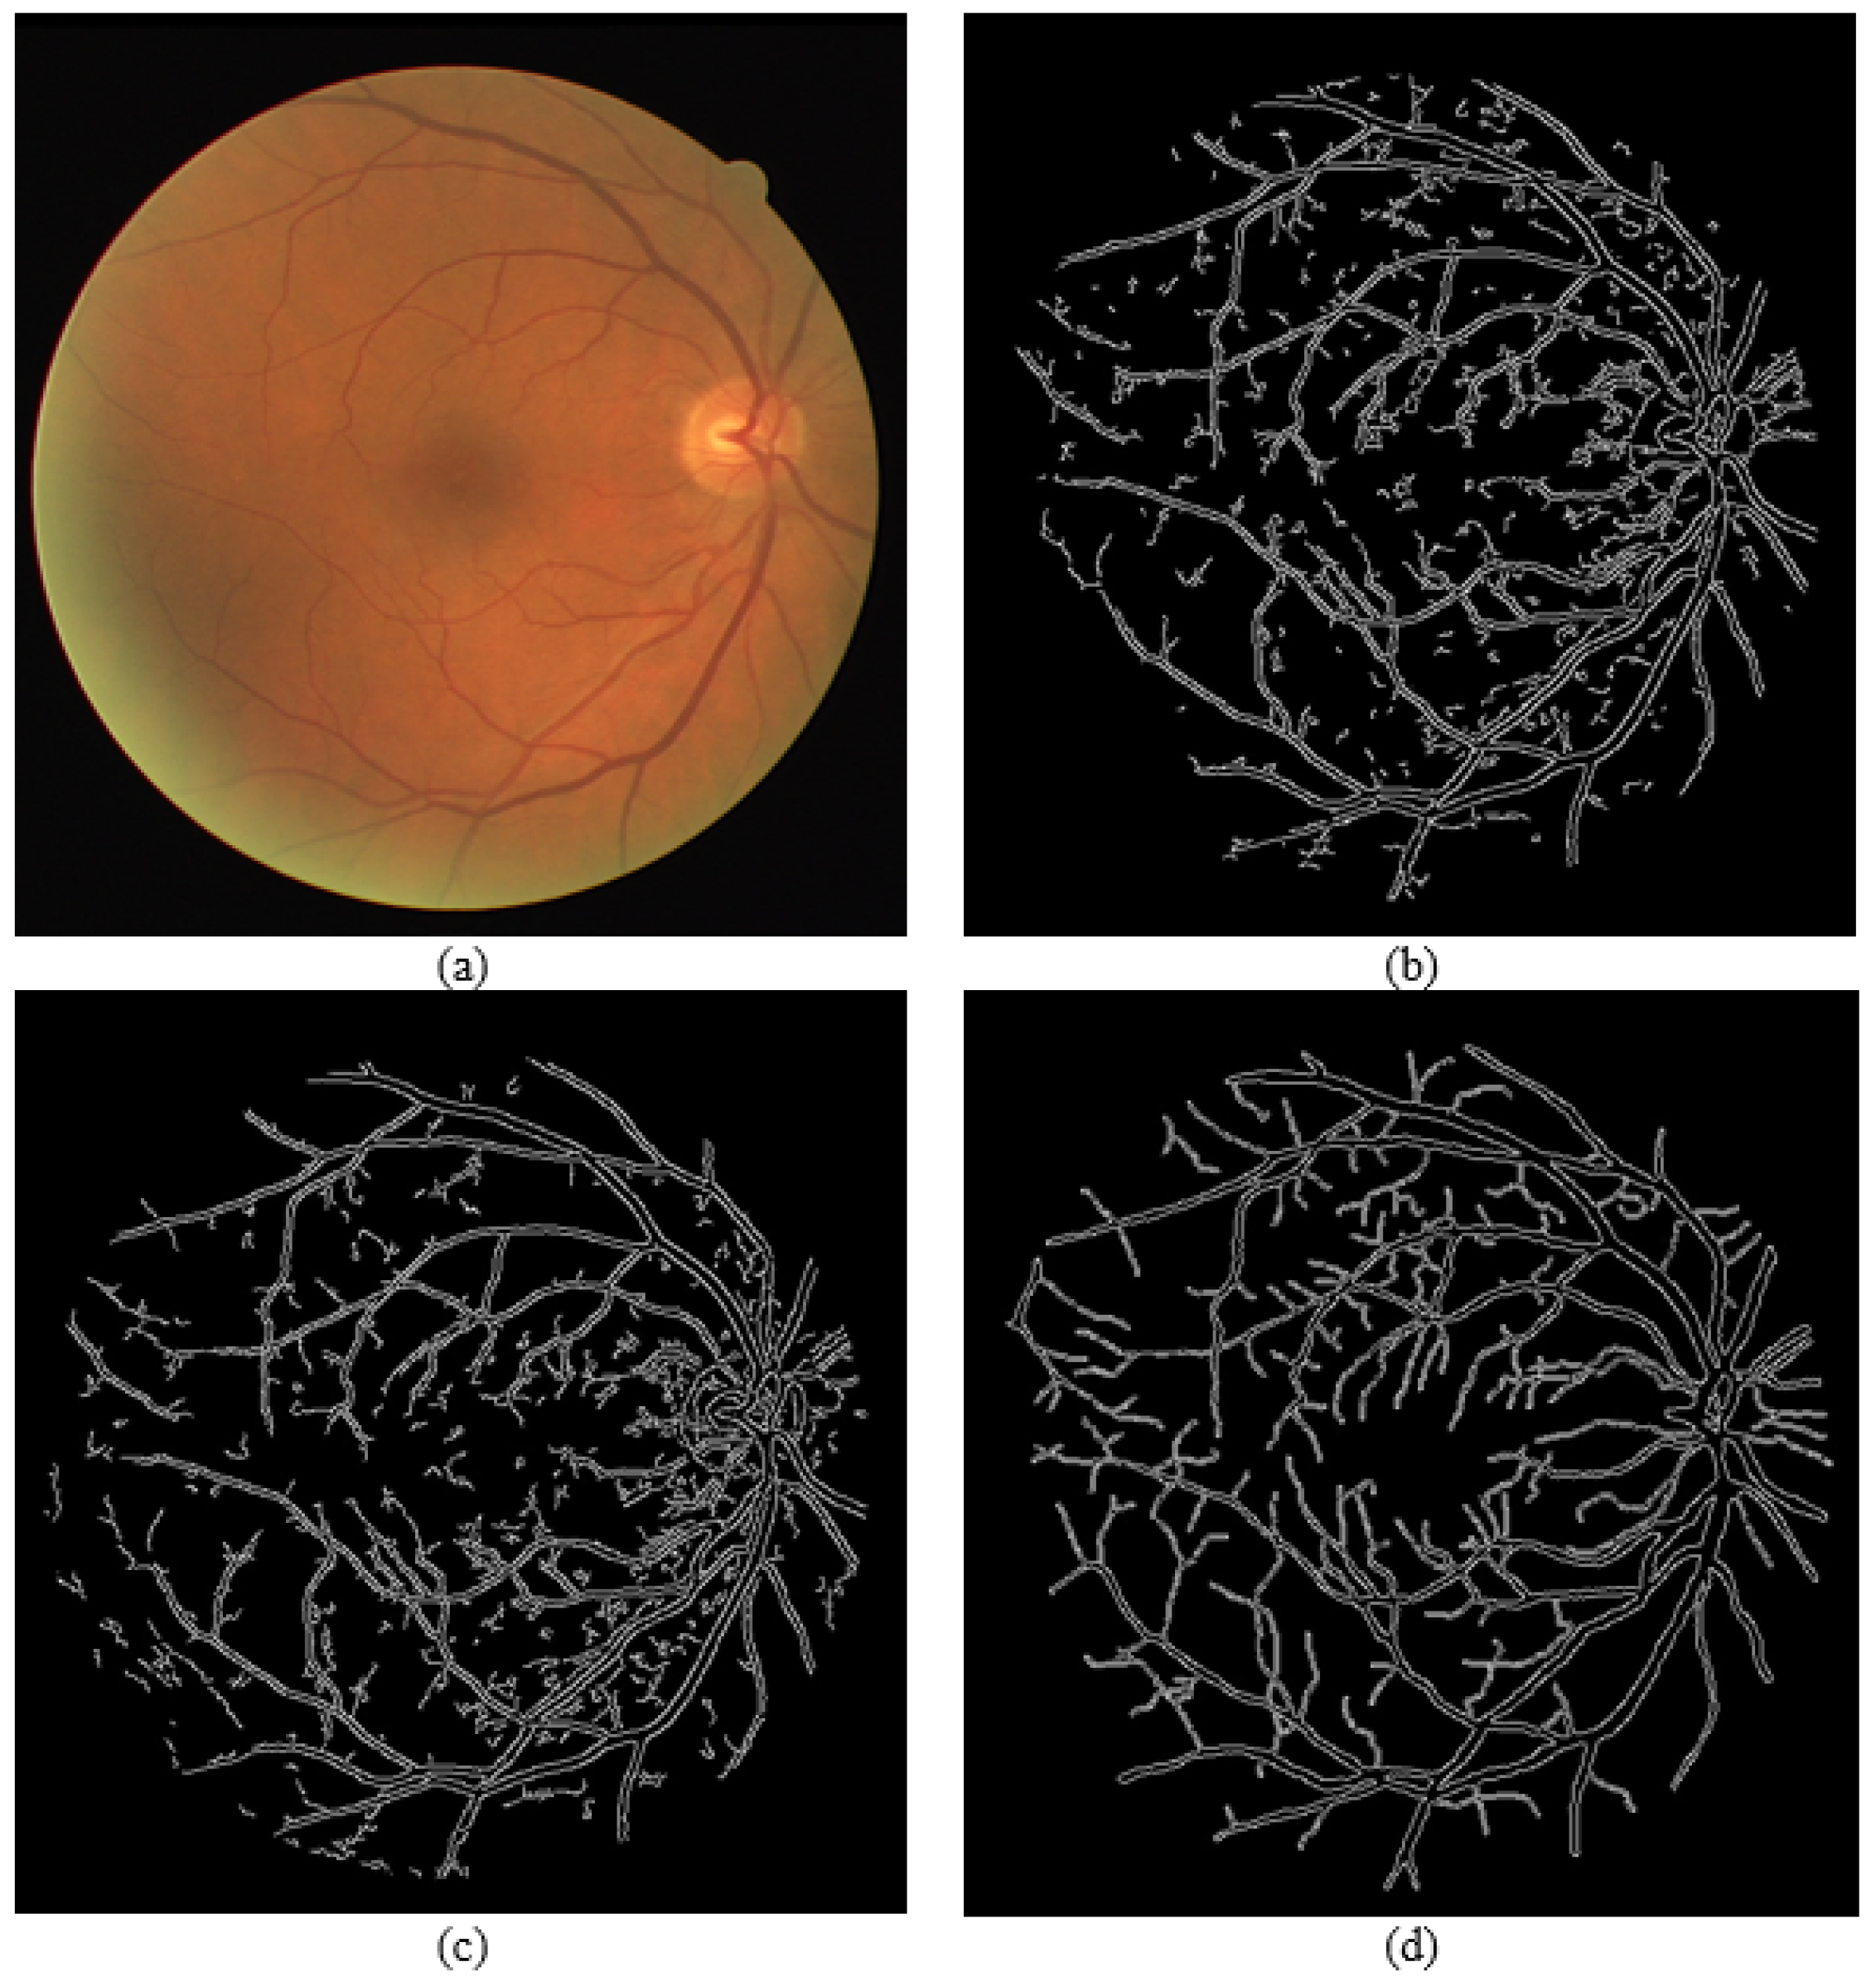

4.3. Edge Detection Technique Results and Evaluation